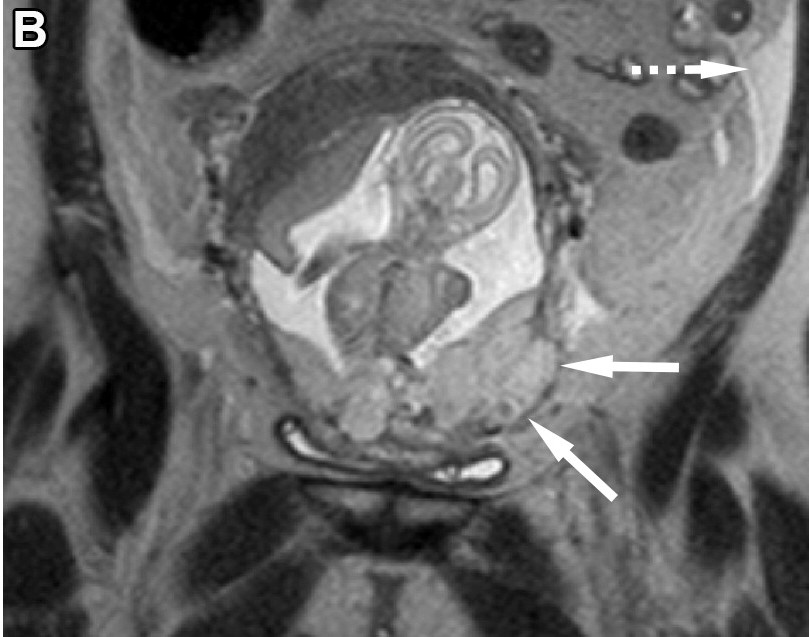

Recognize the MRI features of placenta accreta spectrum disorders, which are increasing in incidence with the rising rate of cesarean deliveries. bit.ly/3VK1gsE @VUMCradiology Krupa Patel-Lippmann Virginia Planz Catie Phillips, MD @moshirimd @VUMC_obgyn

Recognize the MRI features of placenta accreta spectrum disorders, which are increasing in incidence with the rising rate of cesarean deliveries. bit.ly/3VK1gsE @VUMCradiology <a href="/KPatelLippmann/">Krupa Patel-Lippmann</a> <a href="/VPlanz/">Virginia Planz</a> <a href="/CatiePhillips1/">Catie Phillips, MD</a> @moshirimd @VUMC_obgyn

Recent awesomeness from the #BodySection @VUMCradiology! Check out this RadioGraphics update & review article from Society of Abdominal Radiology | SAR⭐️s Krupa Patel-Lippmann, Virginia Planz, @moshirimd, Catie Phillips, MD, & MFM⭐️Lisa Zuckerwise & our former fellow Dr. Ohlendorf! pubs.rsna.org/doi/10.1148/rg…

Recent awesomeness from the #BodySection @VUMCradiology! Check out this <a href="/RadioGraphics/">RadioGraphics</a> update &amp; review article from <a href="/SocietyAbdRad/">Society of Abdominal Radiology | SAR</a>⭐️s <a href="/KPatelLippmann/">Krupa Patel-Lippmann</a>, <a href="/VPlanz/">Virginia Planz</a>, @moshirimd, <a href="/CatiePhillips1/">Catie Phillips, MD</a>, &amp; MFM⭐️<a href="/LCzuckerwiseMD/">Lisa Zuckerwise</a> &amp; our former fellow Dr. Ohlendorf! pubs.rsna.org/doi/10.1148/rg…